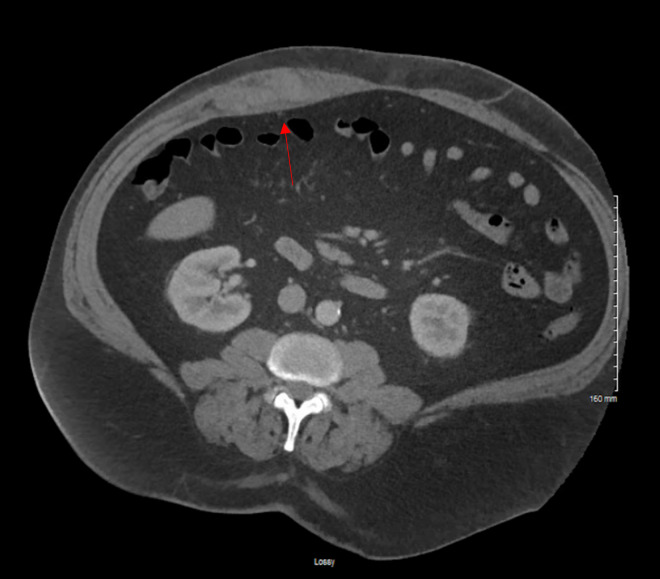

We present a case of a 59-year-old man who arrived to the emergency department with abdominal pain and bruising after coughing. Point of care ultrasound (POCUS) was used to make the diagnosis of rectus sheath hematoma (RSH). This diagnosis was made within minutes of arrival to the ED and subsequently confirmed on computed tomography (CT) of the abdomen. As abdominal ultrasound is a technically straightforward imaging technique which includes a sensitivity that rises about 90%, its utilization to identify rectus sheath hematoma can reduce the rate of CT imaging and time to diagnosis for this pathology.

我们报告了一例 59 岁男子的病例,他因咳嗽后腹痛和瘀伤来到急诊科就诊。急诊超声检查(POCUS)确诊为直肠鞘血肿(RSH)。该诊断是在患者到达急诊室后几分钟内做出的,随后经腹部计算机断层扫描(CT)确诊。由于腹部超声是一种技术简单的成像技术,灵敏度高达 90%,因此利用它来识别直肠鞘血肿可以降低 CT 成像率,缩短诊断时间。